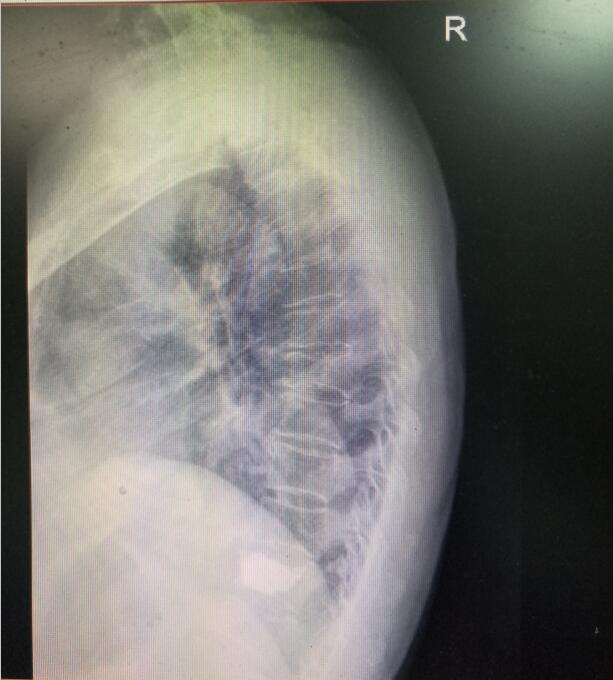

術(shù)前DR(數(shù)字化的x射線)

入院后第四天,由骨傷二科副主任楊陳一、劉永森醫(yī)生、唐國皓醫(yī)生聯(lián)合為患者成功實(shí)施了微創(chuàng)下的經(jīng)皮穿刺椎體后凸成形術(shù)。術(shù)后,患者腰背部疼痛逐漸緩解,術(shù)后第二天即下床活動(dòng)。